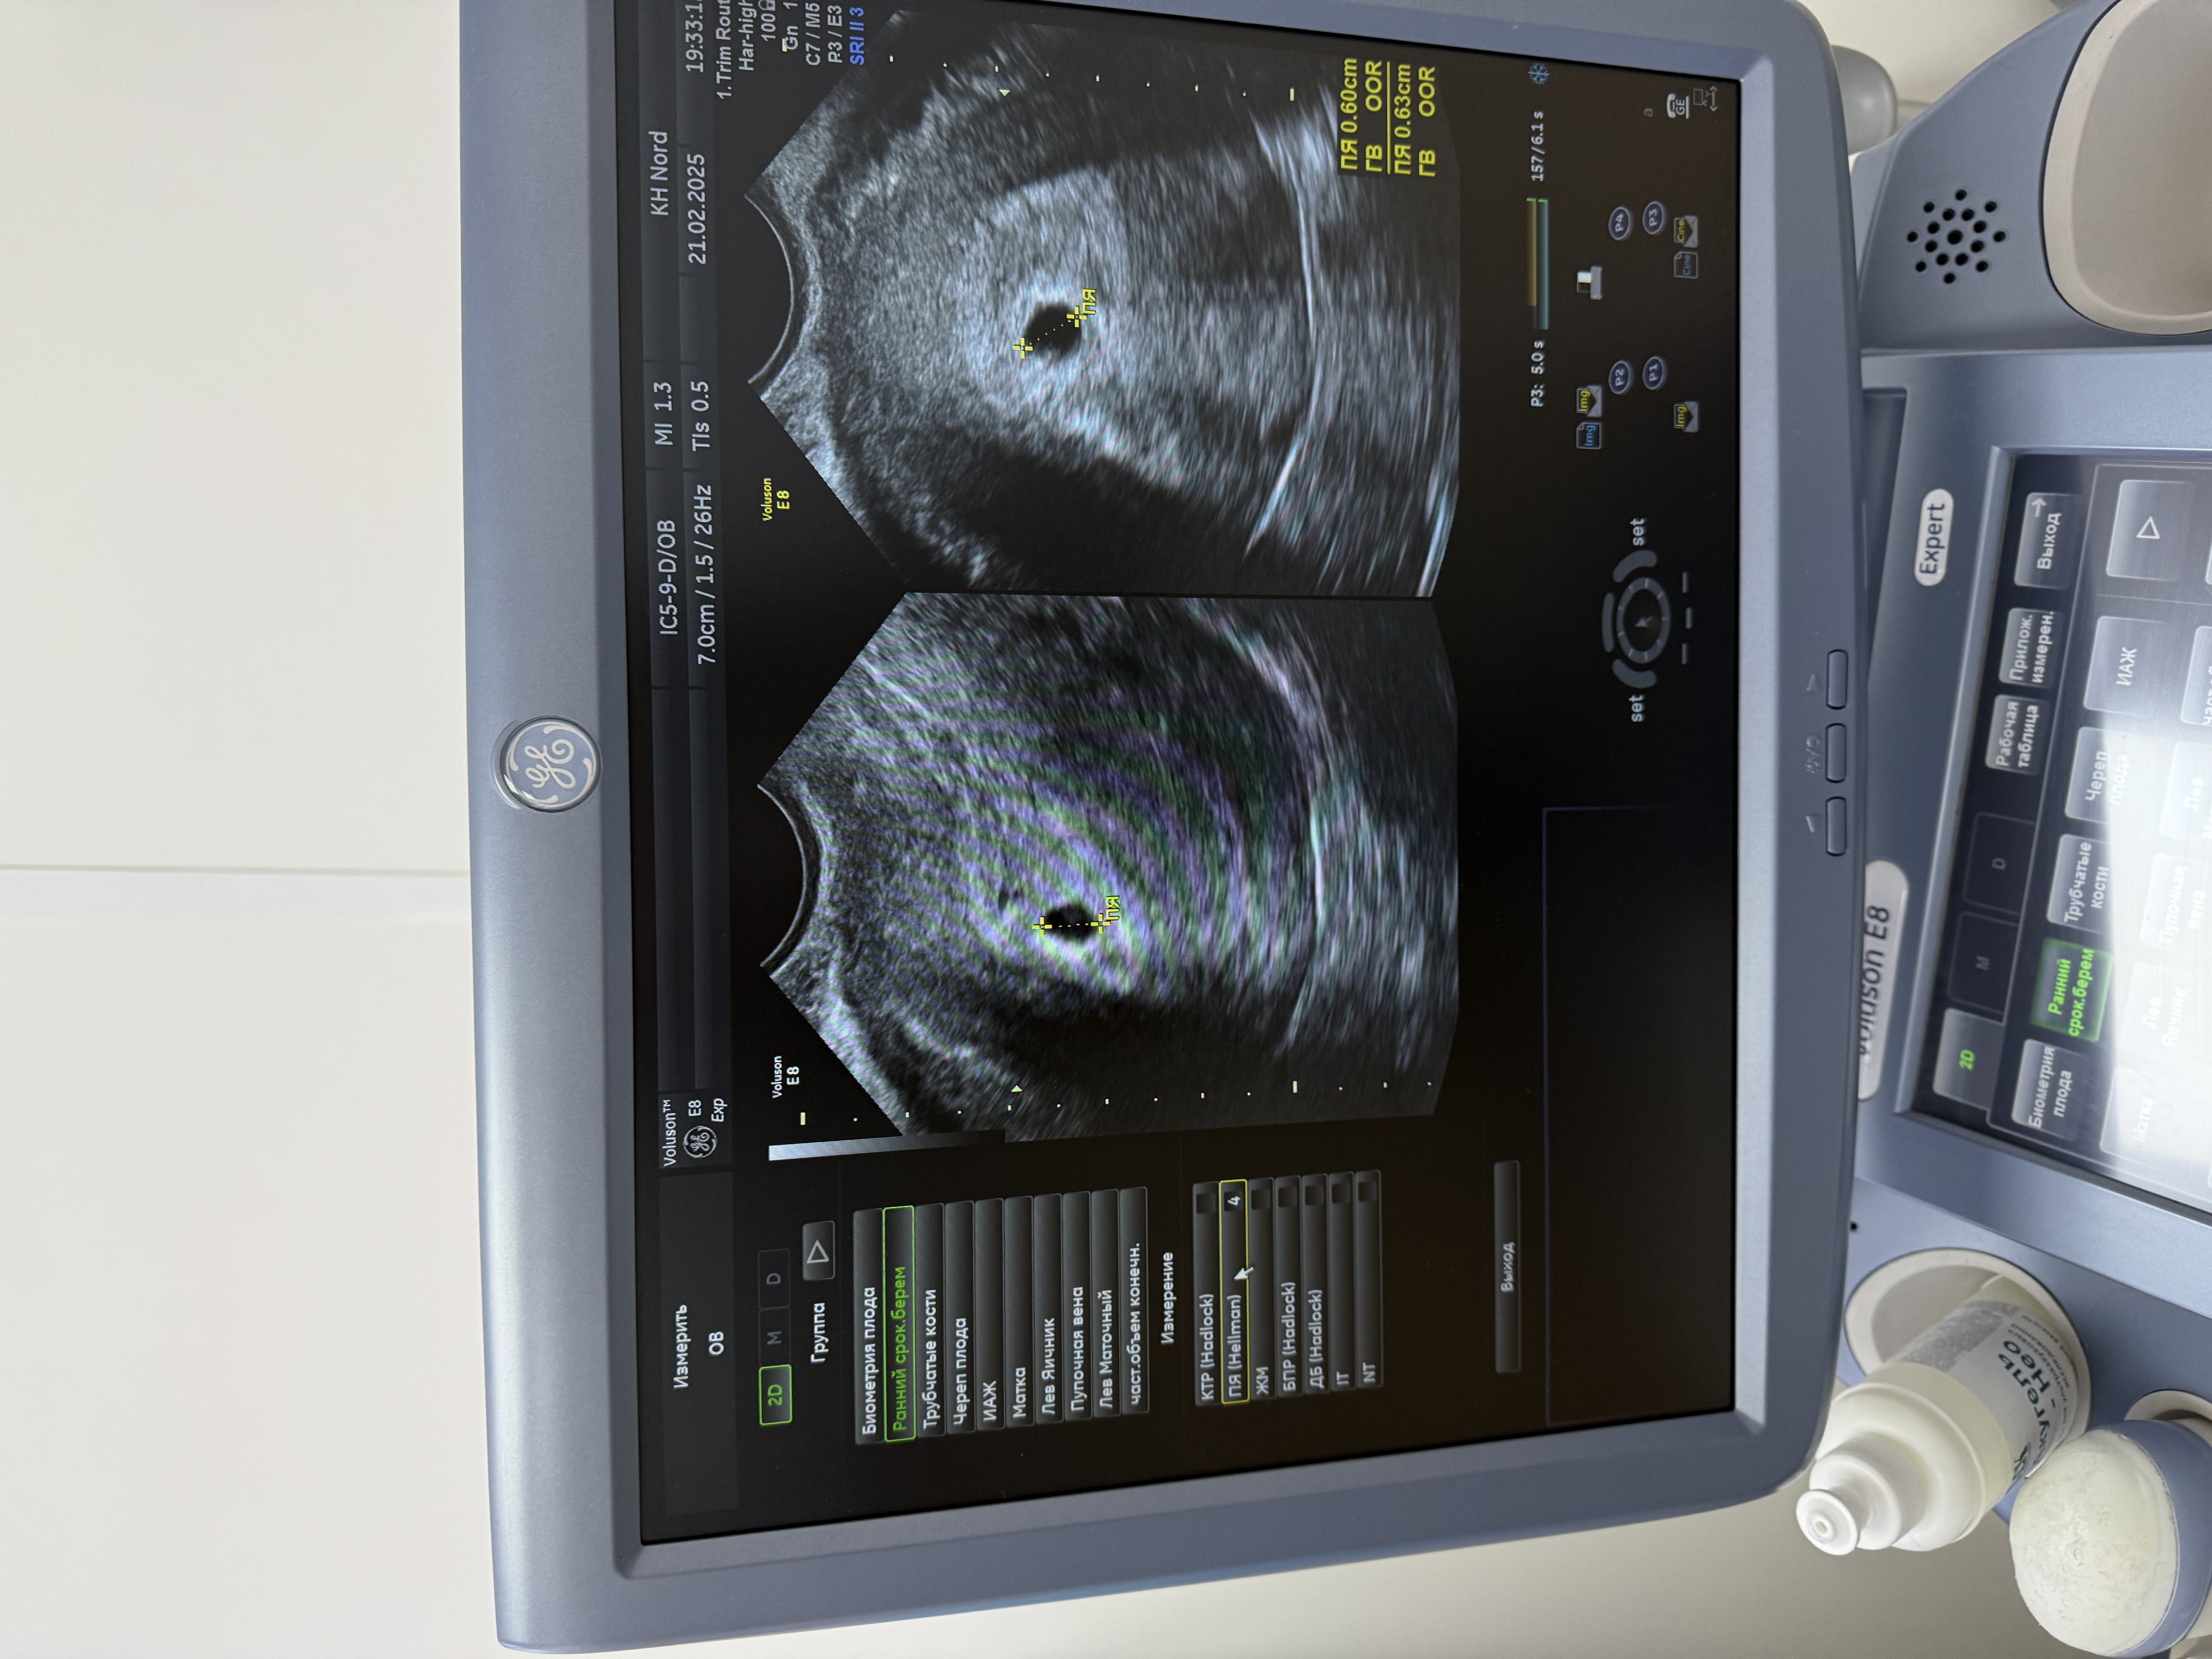

Узи 1 на 21дпп

Результаты УЗИНаша первая встреча и твое первое фото ☺️☺️☺️

мы еще маленькие , пока видно только плотное яйцо 6мм, расти моя крошка 🙏

следующее узи через 2 недели, там уже увидим эмбрион и сердцебиение 💗

Кристина, плодное яйцо 11 мм и желточный мешочек 2,2 мм. Но мне больше и ни чего не написали, ни шейку ни яичники. А вчера ходила всё посмотрели, но я в другом месте платно ходила.